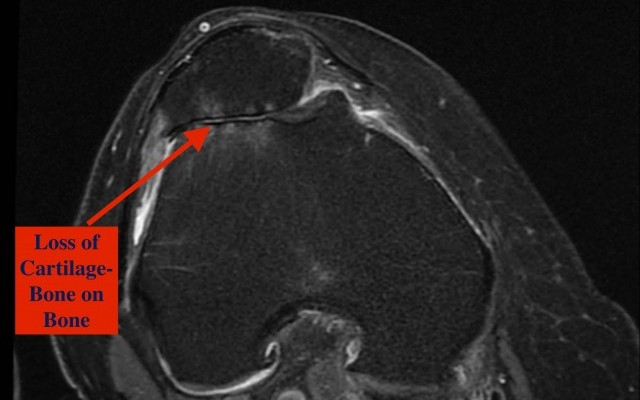

Attached video explains simply what osteoarthritis is and how it manifests as a painful condition.

Many people have knee replacements (also called knee arthroplasty) because they have osteoarthritis. This condition occurs when the cartilage (tissue) that cushions the knee joint wears away. As a result, bone...

Patellofemoral arthritis affects the underside of the patella (kneecap) and the channel-like groove in the femur (thighbone) that the patella rests in. It causes pain in the front of your knee and can make it difficult to kneel, squat, and climb and descend stairs

Patellofemoral arthritis occurs when the articular cartilage along the trochlear groove and on the underside of the patella wears...